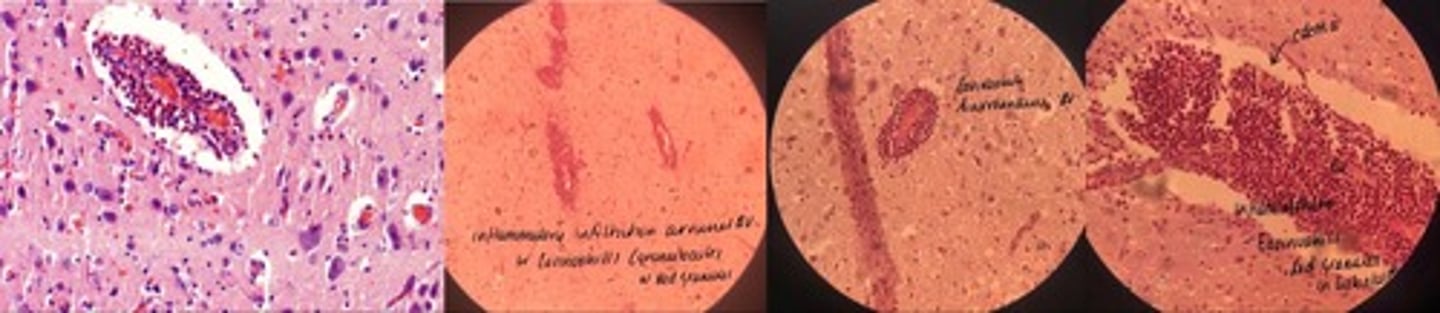

Catarrhal Bronchopneumonia

· thick bronchide walls

· catarral exudate in alveoli lumen (RBCs, leukocytes + mucous)

· congested vessels

· edema separates good + bad

Fibrinous Bronchopneumonia => mosaic appearance

· Acute = capillaries congested + alveoli filled w/light pink fluid

· Red = alveoli filled w/ exudate = fibrin + RBCs

· Grey = lots of neutrophils in lumen

· Resolution = fibrin in strands due to neutrophils enz release

Eosinophilic encephalitis

- MANY eosinophils in perivascular space

- cerebral edema => empty space around bvs + neurons

- neuronal degen + necrosis